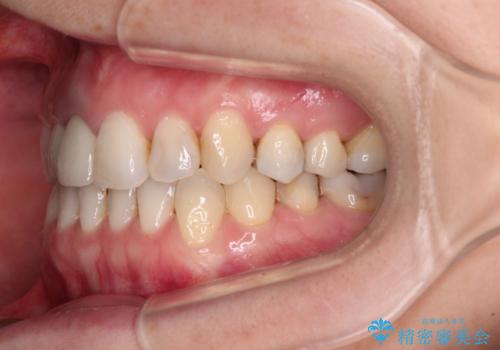

前歯のクロスバイトと治療が必要なむし歯 矯正とセラミックの総合歯科治療

- 前歯が痛いとのことで来院された患者様です。

前歯は根管治療が必要であったため、まずは根管治療を行いましたが、痛みが引いた後、矯正治療や前々から治療が必要と言われてきた歯を治療したいとのことでした。

前歯のクロスバイトはインビザラインで改善し、抜歯が必要な部分はインプラントを、その他むし歯が進行している歯はセラミッククラウンによる補綴治療することとしました。

磨きにくく、何度もむし歯治療を繰り返していた前歯をスッキリと整えることができました。